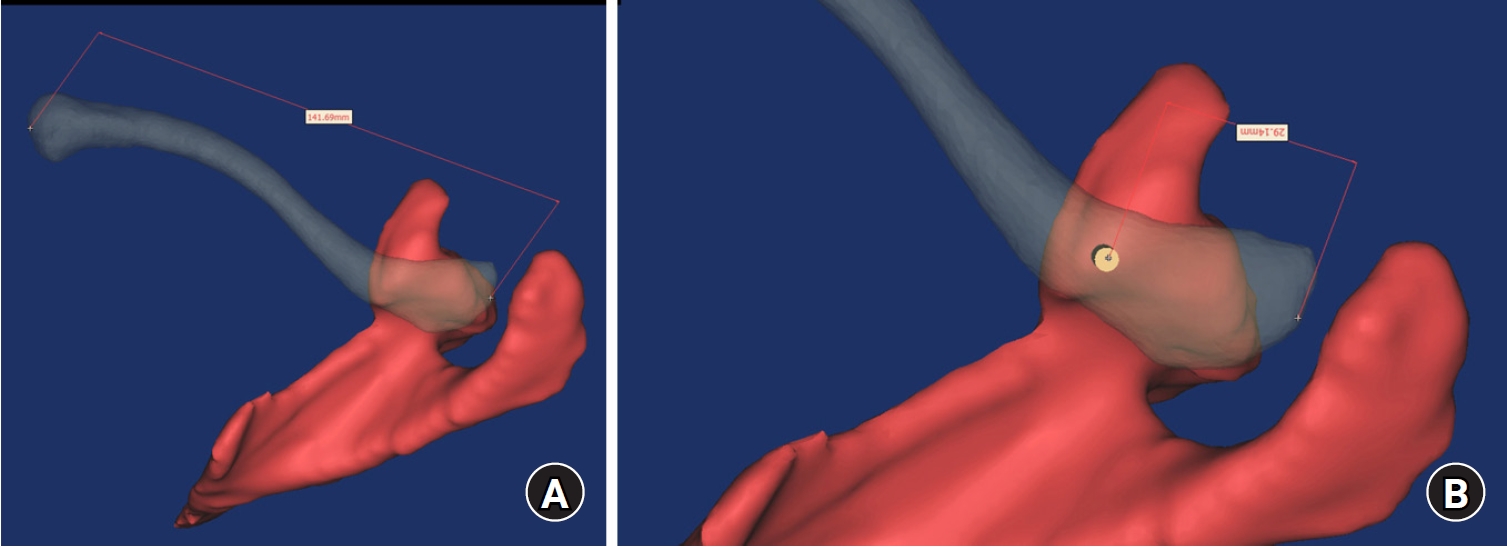

Fig. 1.

Mimics software was used to reconstruct 3-dimentional models of the scapula and clavicle, and the transparency mode was controlled to identify the overlapping area between the clavicle and the coracoid process. The straight distance of the clavicle (A) and the distance between the lateral end of the clavicle and the elevated edge of the coracoid process (B) were measured using software.

Computational Measurement Methods

After obtaining a 3D shoulder model, the straight distance on the upper surface of clavicle was measured using the distant measuring tool of the Mimics software. The distance averaged 141.6 mm (range, 120.7–163.5 mm; standard deviation [SD], 11.2) (Fig. 1). The transparency mode was controlled to differentiate the overlapping area between the upper clavicular surface and the horizontal portion_CP in the cranial view. The straight distance on clavicle between the elevated ridge of horizontal portion_CP and lateral end of clavicle was measured on the upper surface of clavicle and defined as distance_CP (Fig. 1). For the computer-assisted simulation of CC screw fixation through the plate, a virtual 3D model of curved pelvic recon plate (Depuy-Synthes, GmbH) and 3.5 mm cortical screw were created using a 3D sensor (Comet5, Carl Zeiss) in actual size, and placed on the upper surface of distal clavicle using Mimics as with the distal clavicular superior plate fixation (Fig. 2). The ideal position of curved pelvic recon plate (plate) was defined as when the lateral end of plate corresponded to the lateral end of clavicle, the plate was centrally placed on the upper surface of clavicle in the cranial view, and the plate fit well in the anteroposterior (AP) view of the shoulder. After the definitive position of plate was fine-tuned and verified by an experienced surgeon (GHJ), the mutual location of plate holes, horizontal portion_CP and its elevated ridge, and medial border of coracoid process was assessed by controlling the rotation of shoulder model in the cranial and caudal views of the shoulder model. Virtual CC screw fixation through the plate with purchase of the horizontal portion_CP was performed using the Mimics software with a 3.5 mm cortical screw. The corresponding hole and relationship with the adjacent structure were identified.